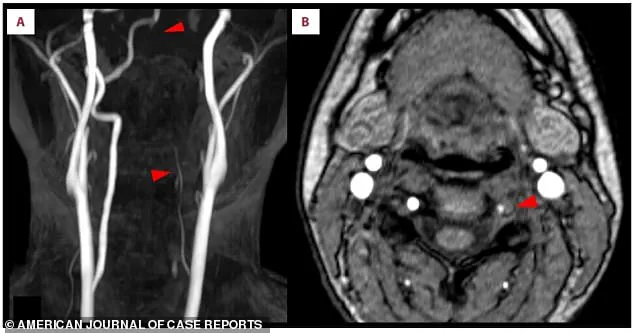

Elena Martinez, a neurologist at the hospital where the woman was treated. "This cross-wiring is why symptoms often appear on the opposite side of the body from the brain injury." MRI scans painted a clear picture of the crisis.

Panel A revealed bright white spots in the right occipital lobe, a region critical for vision.

These bright signals, called hyperintensities, indicated a lack of blood flow due to the stroke.

Panel B showed a missing section of the right posterior cerebral artery, a key blood vessel, confirming the blockage.

Lower arrows on the same scan pointed to the left vertebral artery in her neck, which appeared faint or broken. "This artery is like the lifeline to the brain," explained Dr.

Martinez. "When it’s compromised, the brain is starved of oxygen, and that’s when the damage begins." Scan A further revealed that the left vertebral artery, a vital pathway for blood flow to the brain, was thin and faint, suggesting restricted circulation.

Scan B delivered the final confirmation: a crescent-shaped blood clot nestled within the artery’s wall. "That clot was the enemy," said Dr.